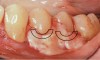

Fig 3. Tooth No. 28 had a Class V filling that failed with recurrent decay (Fig 3). A tuberosity CTG with a 1.5 mm thickness was placed, and after 1 year there was no keloid-like appearance (Fig 4).

Figure 3

Fig 4. Tooth No. 28 had a Class V filling that failed with recurrent decay (Fig 3). A tuberosity CTG with a 1.5 mm thickness was placed, and after 1 year there was no keloid-like appearance (Fig 4).

Figure 4

Class V fillings are artificial materials that tend to fail at the apical extent and have poor long-term success (Figure 3).1 Conversely, CTGs are natural and attach to the root surface and have high long-term success (Figure 4).1

Regarding the avoidance of a gingivoplasty procedure later, there appears to be nothing in the literature describing the ideal thickness of a tuberosity CTG. From palatal and allograft thickness recommendations, one could hypothesize that the thickness be between 0.75 mm and 2 mm. This article will propose a graft thickness between 1 mm to 1.5 mm (Figure 3 and Figure 4) for the optimal functional and esthetic outcome and will discuss various procurement and fileting techniques.